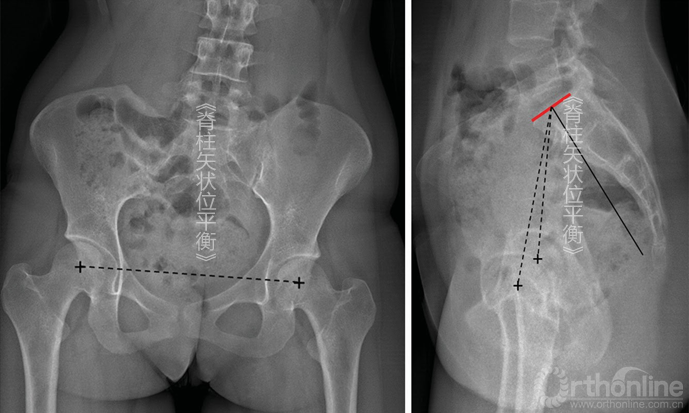

医师在测量PI角时可能遇到很多困难。骶骨终板及前后边界通常容易分辨,但是因为传统的成像设备很难将双侧股骨头对齐,所以股骨头中点经常容易混淆:

①股骨头垂直移动(图5-2)。这是由于X线束的倾斜度与下肢长度的差异造成的。此时引用双侧股骨头连线中点线测量PI角是可以的。

图5-2 因为双下肢不等长导致股骨头股骨头垂直立线偏移,对PI的测量几乎没有影响

②股骨头水平移动(图5-3)。此时测量无法进行,其影响脊柱矢状位平衡分析。这是因为骨盆水平旋转,此时的X线不是真实的侧位片,且如果骨盆旋转较大,测量得到的PI角会受到影响,这样的影像便不能采纳。

图5-3 因骨盆旋转导致股骨头水平立线偏移,会导致PI测量结果误差较大